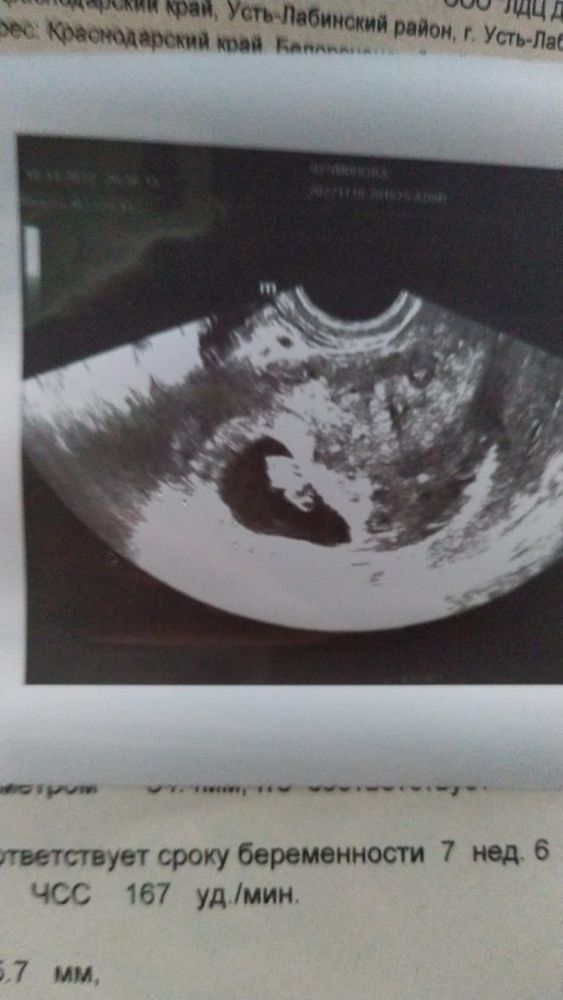

Похоже на тонус. У меня на 5 недели вообще было сплющенное из-за тонуса. Ставила папаверин и дюф назначили. Ещё врач спросил разве не болит? Вроде тонус. Ну как только спросил, сразу заболело)))

Нормальная реакция матки на узи, особенно трансвагинальное) она в тонусе

Яна, у меня очень чувствительная матка и сразу входит в тонус от узи) Просто на таком сроке, это не чувствуется. А сейчас я четко ощущаю тонус, от узи. И это нормально 🤷‍♀️. У меня тоже такое было плодное яйцо, просто из-за тонуса, матка сжимается и оно деформируется, но нужно понять, что это происходит в момент)

Да,возможно вы имеете ввиду деформация плодного яйца и угроза?

У меня было, никакой угрозы не ставили, малыш рост яйцо стало круглым, др 9 неделе неправильной формы был

Это тонус, вставляйте папаверин на ночь, несколько дней подряд.